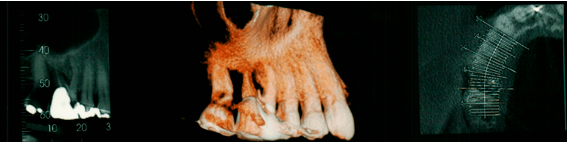

Quando falamos em processo alveolar, estamos muito além do tecido ósseo ou uma simples articulação denominada especificamente de Gonfose. Falamos de um sistema de amortecimento e absorção de impactos altamente especializado e dependente do dente. Logo, a perda de dente resulta em mudanças tanto horizontais como verticais das dimensões dos tecidos duros e moles. Essas alterações podem ser acompanhadas clinicamente através de: sondagem clínico-cirúrgica, medições por imagens tomográficas e medições em modelos de estudo1.

Estudos mostram que a taxa de reabsorção óssea na face vestibular pode chegar a 56%, enquanto que a reabsorção óssea na face lingual pode atingir 30% em áreas de implantes com superfícies tratadas, colocados no momento das exodontias2.

Geralmente, o padrão de reabsorção da parede vestibular apresenta-se mais grave que a lingual. A reabsorção observada nos tecidos duros no sentido horizontal (vestíbulo-palatino) pode variar de 29% a 63% comparado ao vertical (inciso-cervical), que varia de 11% a 22% em um período de observação de três a sete meses. Acredita-se que essa diferença de porcentagem ocorra devido à presença de dentes próximos à área avaliada ou a espessura da parede vestibular3.